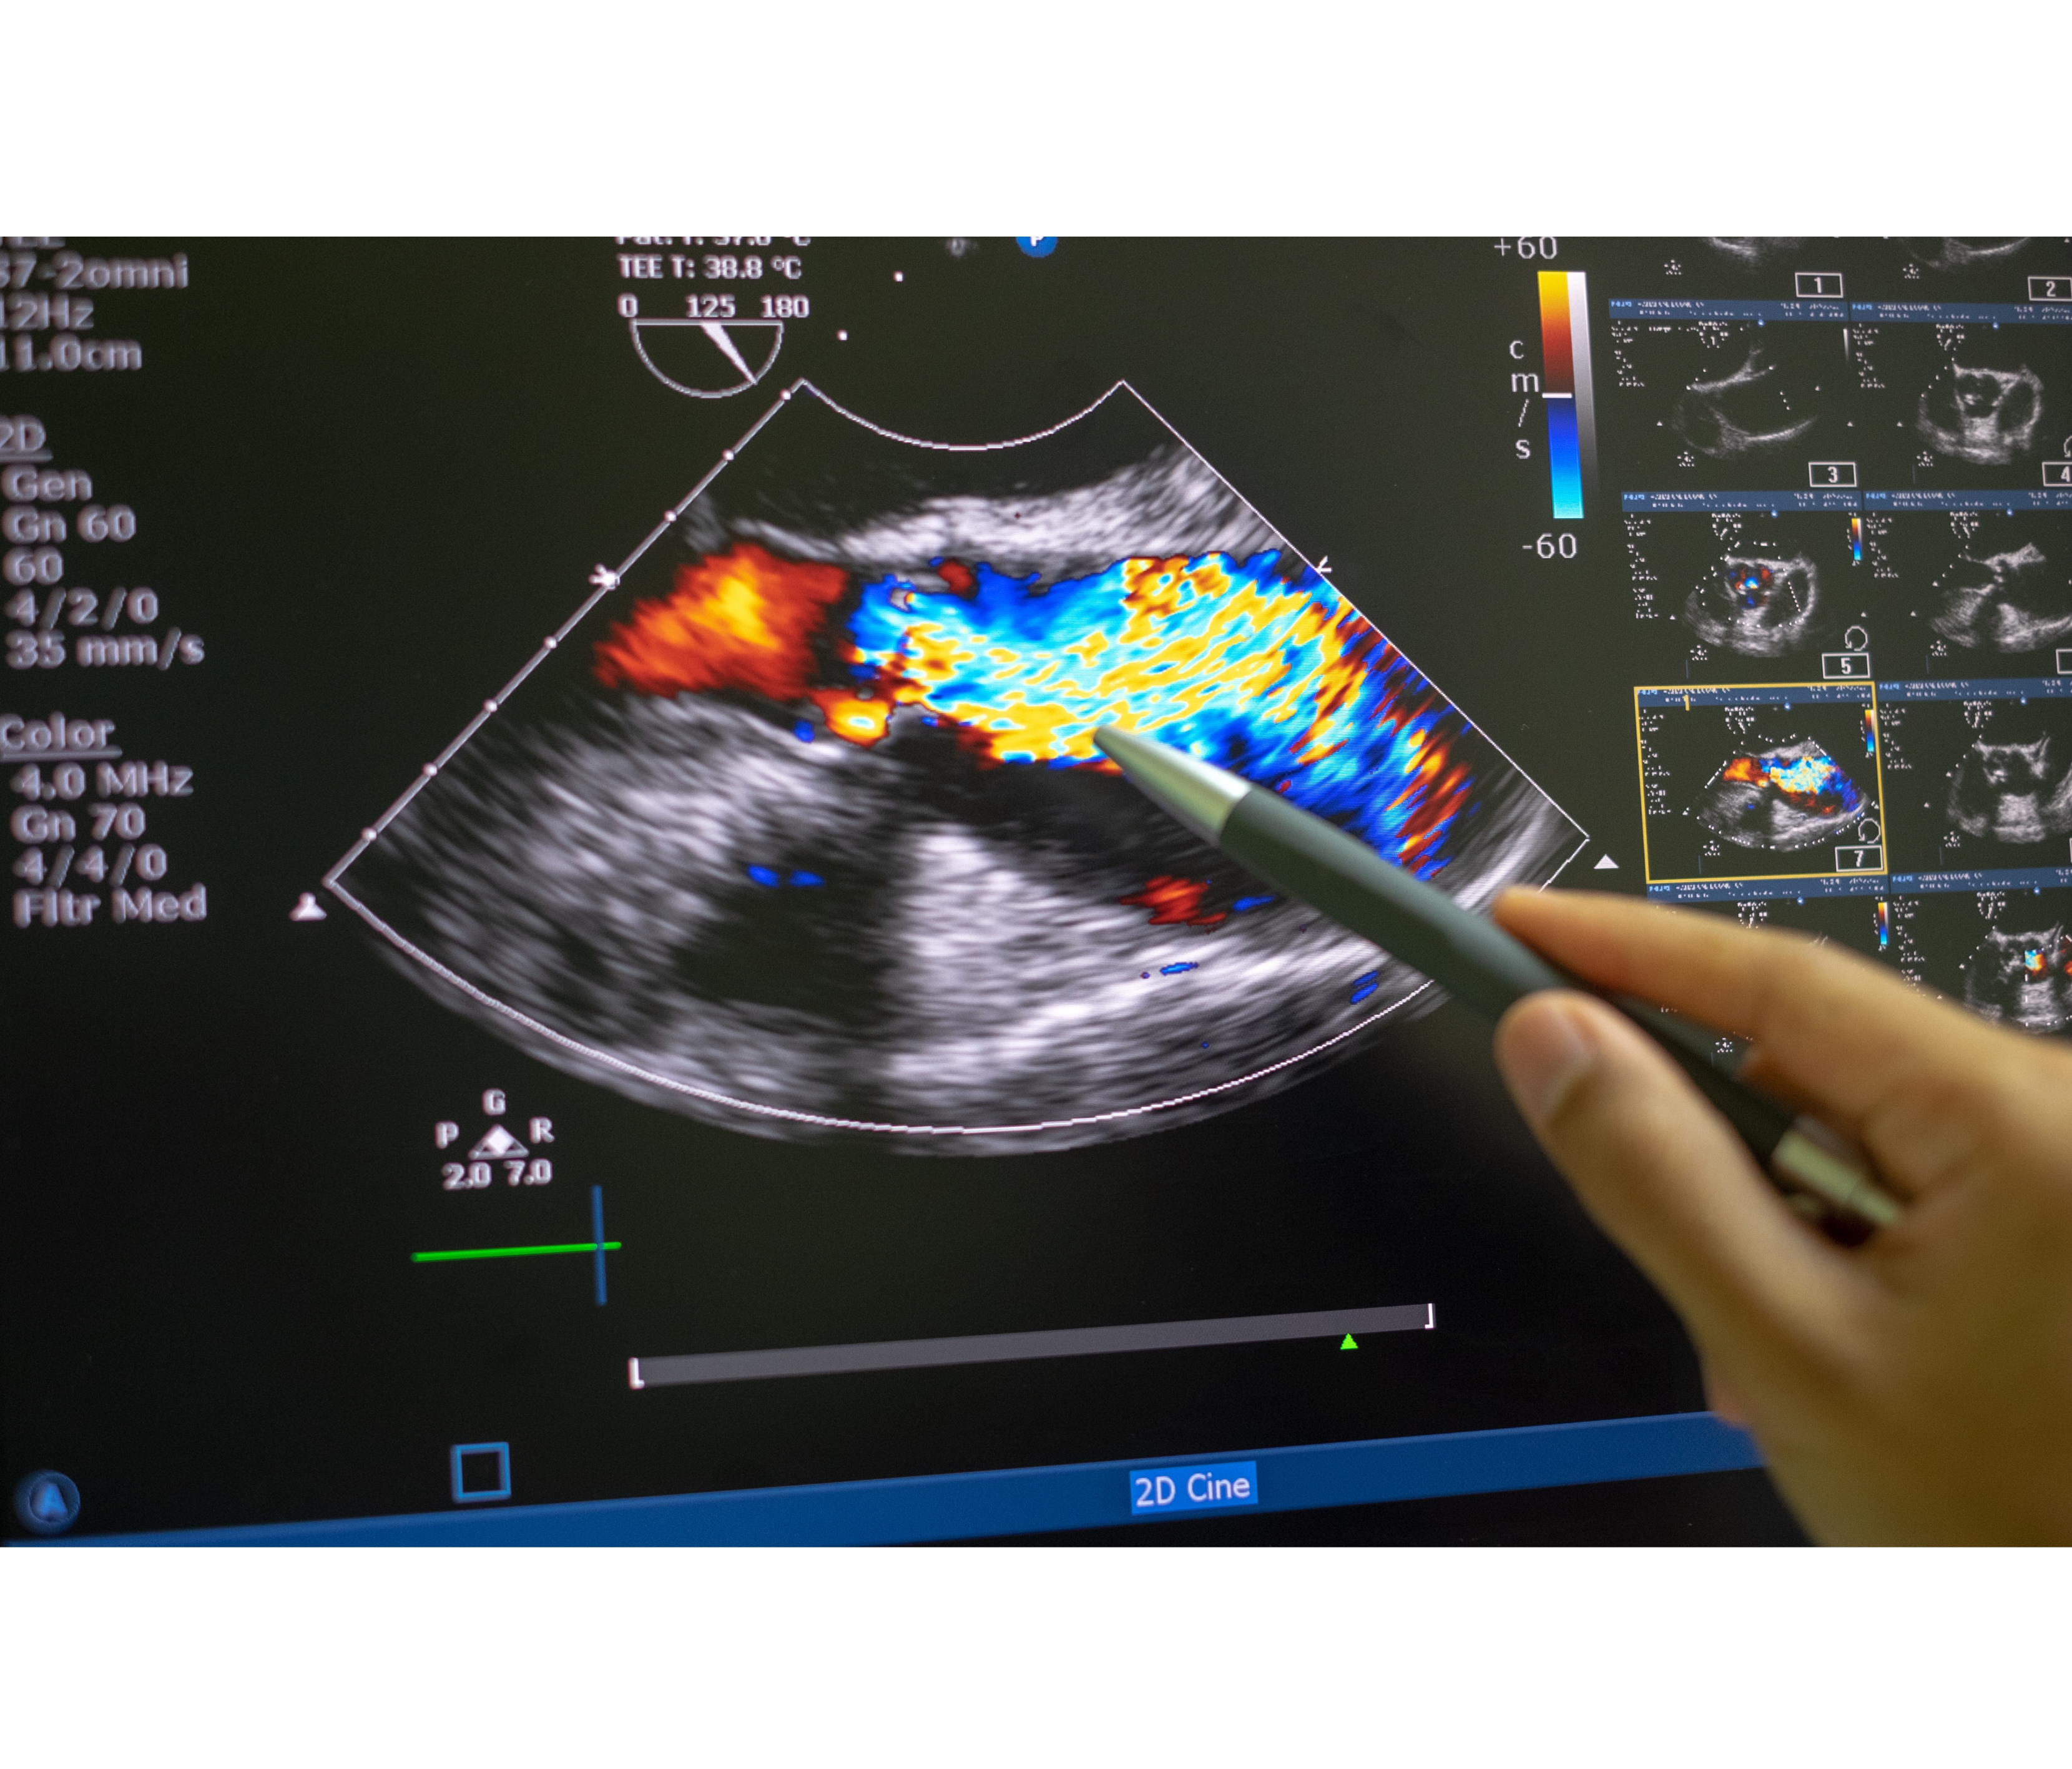

2D Echocardiography

Fine diagnostic and evaluation via echocardiography for heart-related issues in both adult and pediatric patients.